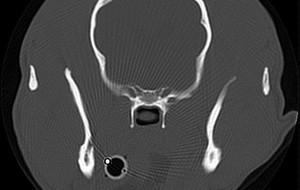

This month's case from the CT/MRI Society of the ACVR is a CT scan provided by Dr. Rob McLear. It has a holiday theme... … [Read more...]

This month we have a case from Dr. Alex zur Linden of the University of Guelph. These cases are sponsored by the CT/MRI Society of the ACVR and are available to view for 1 month. For full access to the case archive, join the CT/MRI society at the ACVR website. Access all images and … [Read more...]

This month's CT/MRI Society case is presented by Jennifer Reetz, from the University of Pennsylvania. If you'd like unlimited access to all CT/MRI society cases, please join the society at the ACVR website. Cases provided here are available to the public for viewing for a period of one … [Read more...]

This month's CT/MRI Society case is from Shannon Holmes at the University of Georgia. Just a reminder that these cases are available to view for 1 month only. If you'd like to have access to all of them, become a member of the ACVR CT/MRI Society. Enjoy! Access full case information and all … [Read more...]